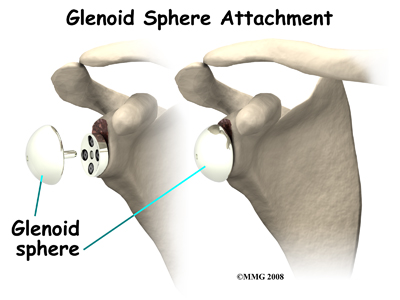

In the traditional artificial shoulder prosthesis, the glenoid prosthesis is a shallow socket made of plastic and the humeral component is a metal stem attached to a metal ball that nearly matches the anatomy of the normal shoulder. In the reverse shoulder replacement, the ball and the socket are reversed such that the ball sticks out of the shoulder itself.

The humeral component is a combination of a metal stem that fits into the marrow cavity of the upper humerus and, on top of the metal stem, a plastic socket. This plastic socket fits onto the humeral component to create a ball and socket type bearing. The glenoid component is usually made of two parts: a metal tray and a metal ball. The metal tray (base plate) attaches directly to the bone. This base plate is inserted into a small peg hole drilled into the bone and is secured with special screws through the base plate into the bone. Attached to that metal tray, there is a metal ball that will fit into the plastic socket attached to the humeral component. The plastic is very tough and very slick, much like the articular cartilage it is replacing. This plastic is so tough that you could actually ice skate on a sheet of this plastic without causing it much damage.

Finally, the humeral component and the glenoid component are inserted.